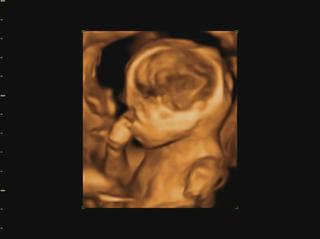

Ahojte kočky, konečne mam trošku času tak si idem spätne prečítať čo ste napísali... a pochváliť vám krásne brušinká 😀 medzi tým Vám pridám moje brušo a našu Izzy neposednú. Máme aj video, ale to som dala len FB, lebo tu sa pridať nedá. Fotky aj video je trochu rozmazané, lebo mala v kuse so sebou narabala... a ano pipik nam nedorastol... 😀